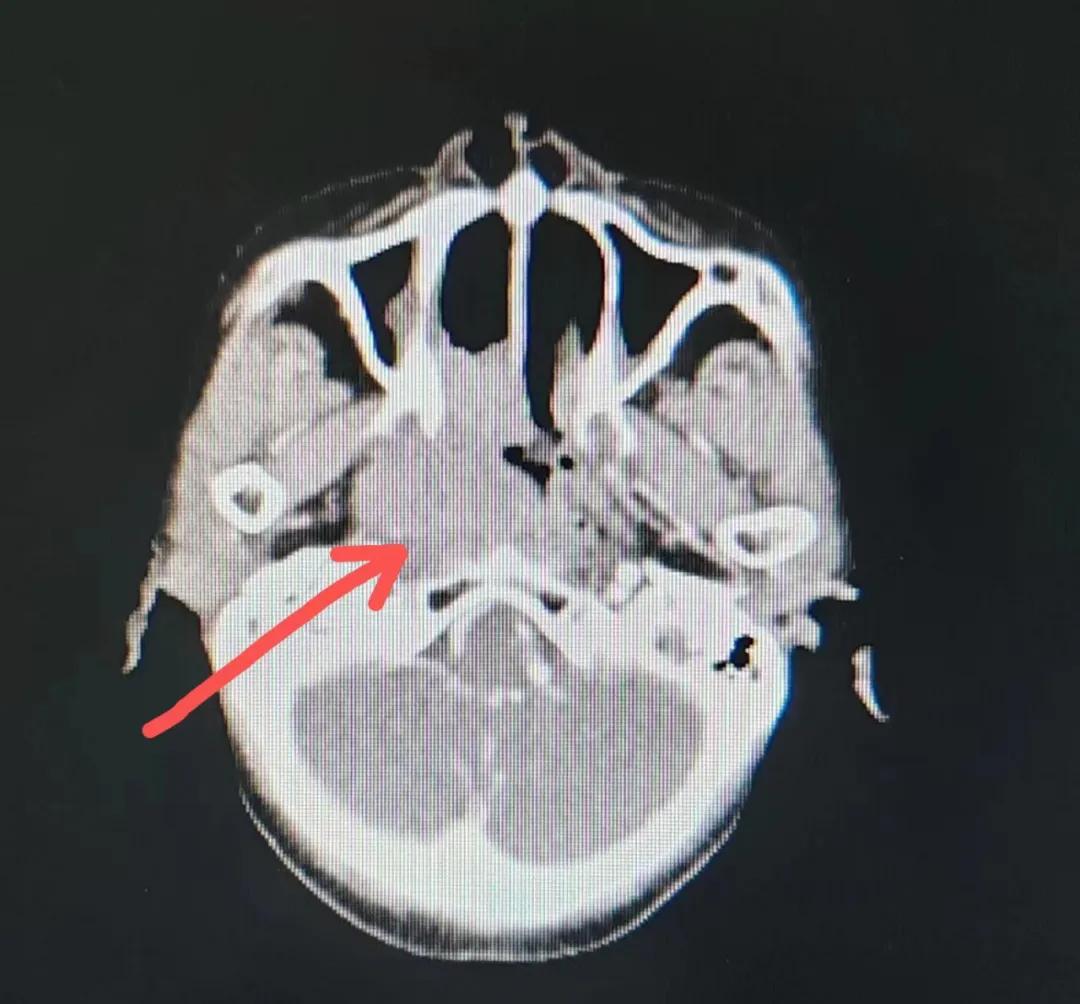

70歲的彭阿姨,5個(gè)月前因鼻部瘙癢伴流血不止在當(dāng)?shù)卦\所治療,瘙癢和出血癥狀不但沒有得到有效控制,反而進(jìn)行性加重,并出現(xiàn)鼻腔堵塞、進(jìn)食困難,經(jīng)外院病理活檢確診為“鼻腔惡性淋巴瘤”。不斷加重的病痛已嚴(yán)重影響了老人的生活質(zhì)量,為求診治,患者及家屬于今年2月份慕名來到了市二院放療科。

治療前

老人因鼻部腫物堵塞鼻腔并且侵犯鼻咽導(dǎo)致鼻塞、疼痛、吞咽困難,身心都備受煎熬,趙亮主任在詢問其病史期間幾度落淚。趙亮主任向患者及家屬解釋說:“現(xiàn)代放療比過去的傳統(tǒng)放療設(shè)備先進(jìn),技術(shù)不斷提升,能對(duì)腫瘤區(qū)域的照射劑量進(jìn)行優(yōu)化,做到準(zhǔn)確定位、精準(zhǔn)照射,同時(shí),最大限度地降低正常組織的受量,對(duì)全身情況影響很小。”

考慮到患者年齡較大、體質(zhì)差,手術(shù)難度大,且常規(guī)的放射治療難以保護(hù)患者晶體造成患者雙眼視力損傷,放療團(tuán)隊(duì)以最快的速度制定了精準(zhǔn)放射治療方案并開始為其實(shí)施治療。僅僅數(shù)日后,老人腫塊出血即得到控制,腫塊明顯縮小,放療20次后腫塊迅速縮?。?/div>